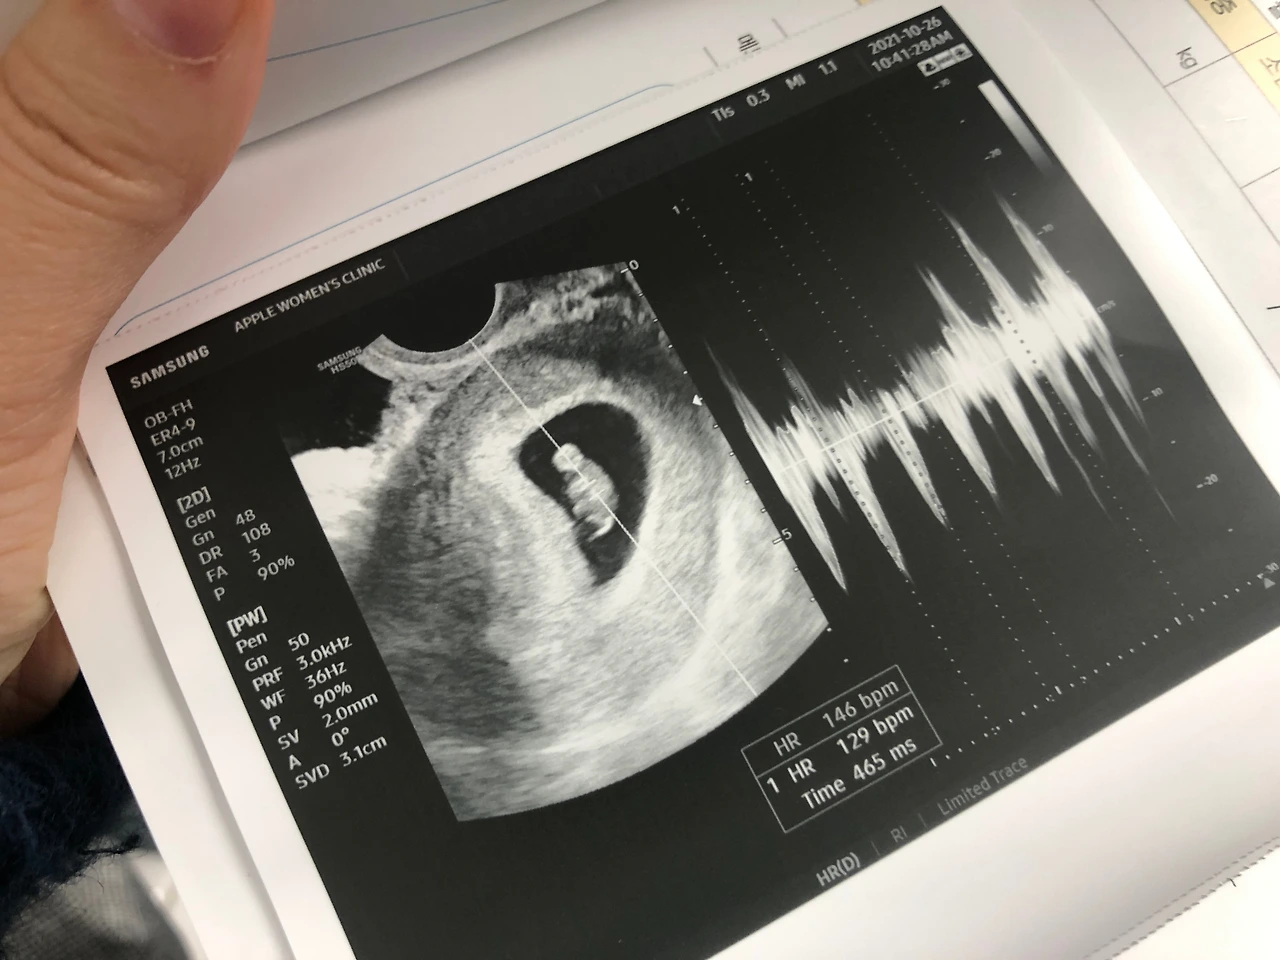

사실 좀 걱정했는데, 심장도 잘 뛰고 아주 잘 자라고 있더구나!